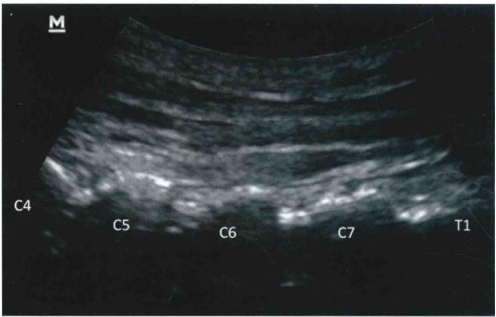

采用平面内技术,在选定的穿刺点,以长3.5英寸带芯穿刺针在超声探头的下方以小关节为靶点从尾侧向头端方向进针( 图9和图10 )。

图9 / 超声引导下颈椎小关节内阻滞